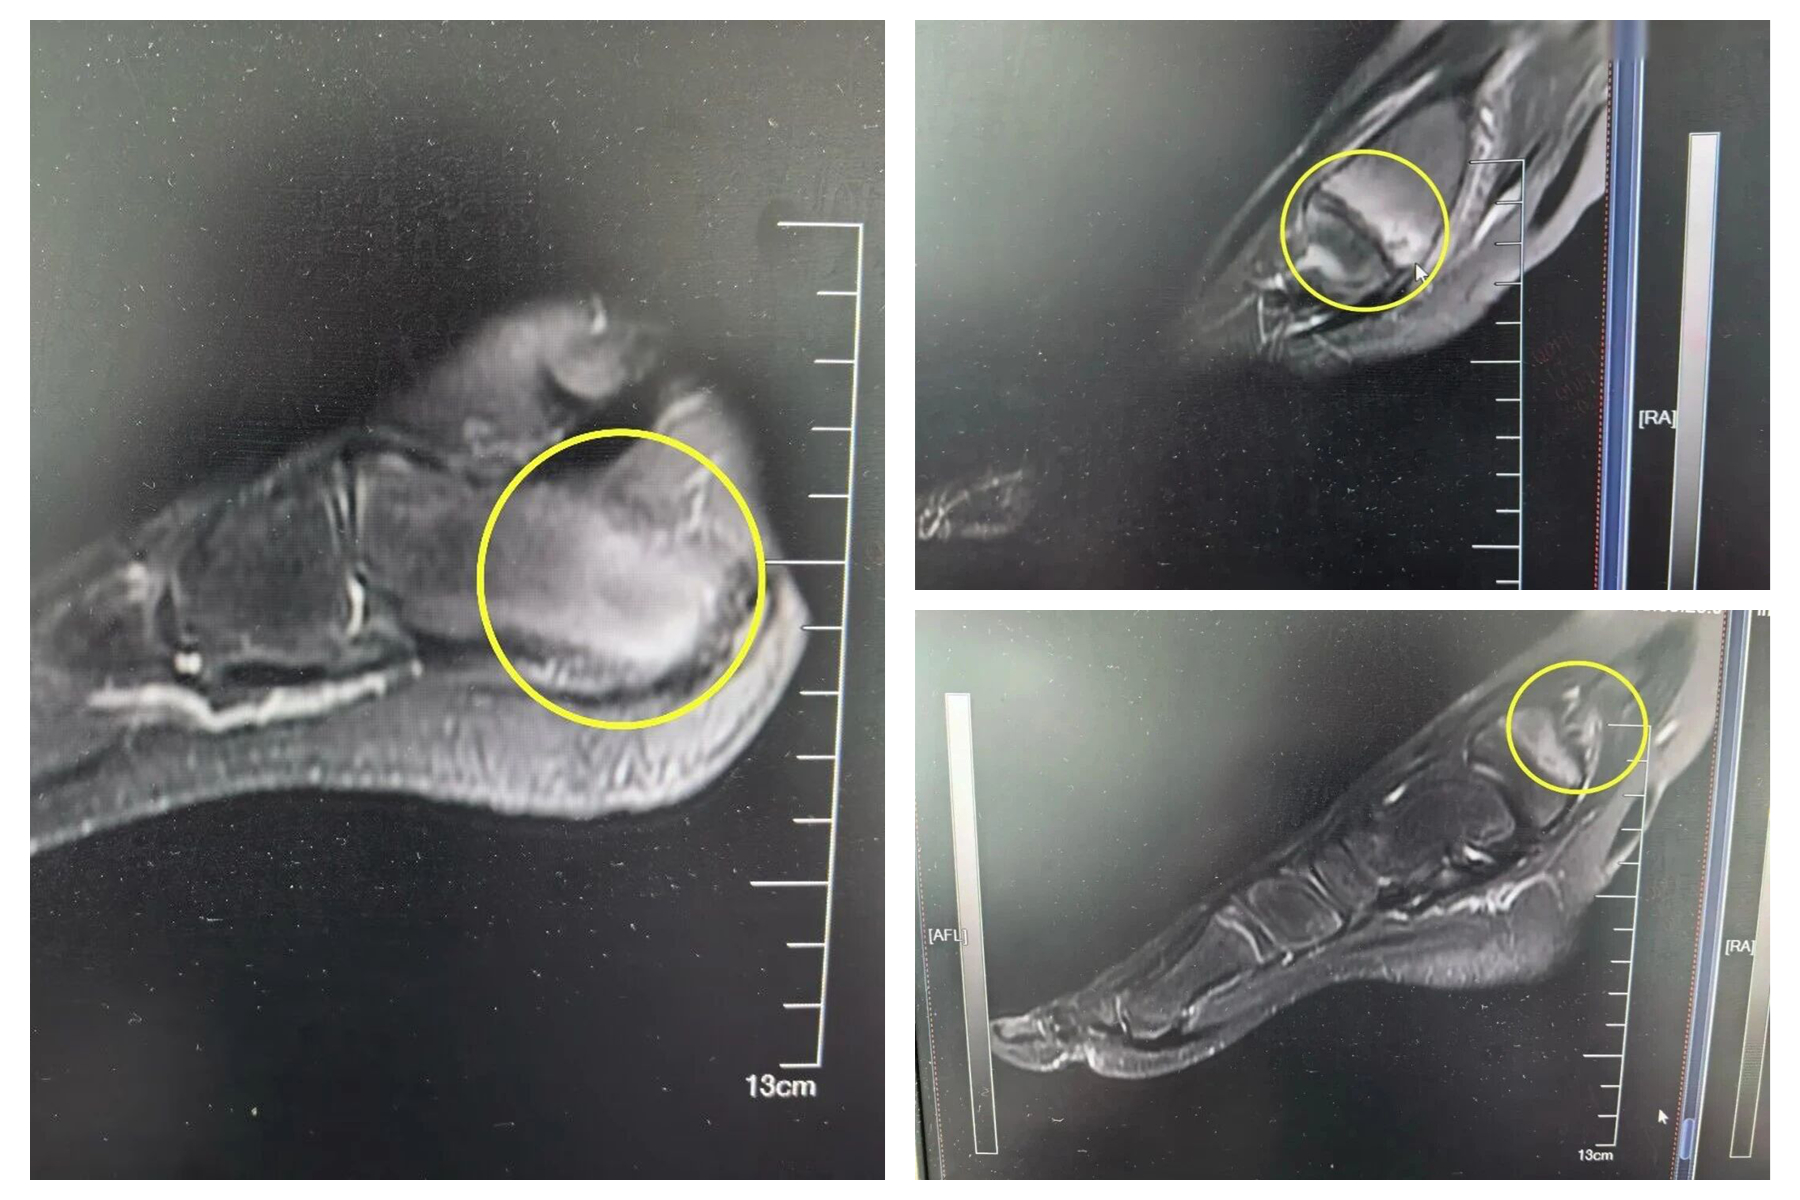

顺着这一思路,进一步完善关节影像学检查,结果显示皮皮存在多发骨质破坏、骨髓水肿,同时炎症指标升高,而类风湿因子、HLA-B27等阴性,排除肿瘤、感染性、自身免疫疾病依据,经综合分析,最终确诊为慢性复发性多灶性骨髓炎。